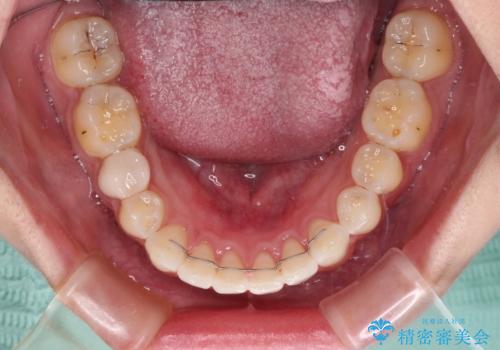

- 前歯の歯列不正を気にして来院された患者様です。

インビザラインでの矯正治療を希望されていましたが、奥歯の咬み合わせがインビザライン単独では改善困難と判断されたので、補助装置を併用することとしました。

まずは裏側の装置やワイヤー矯正を用いて歯列幅の狭い上顎を側方に拡大しつつ全体を後方に移動させ、その後インビザラインにて歯列を整えることとしました。